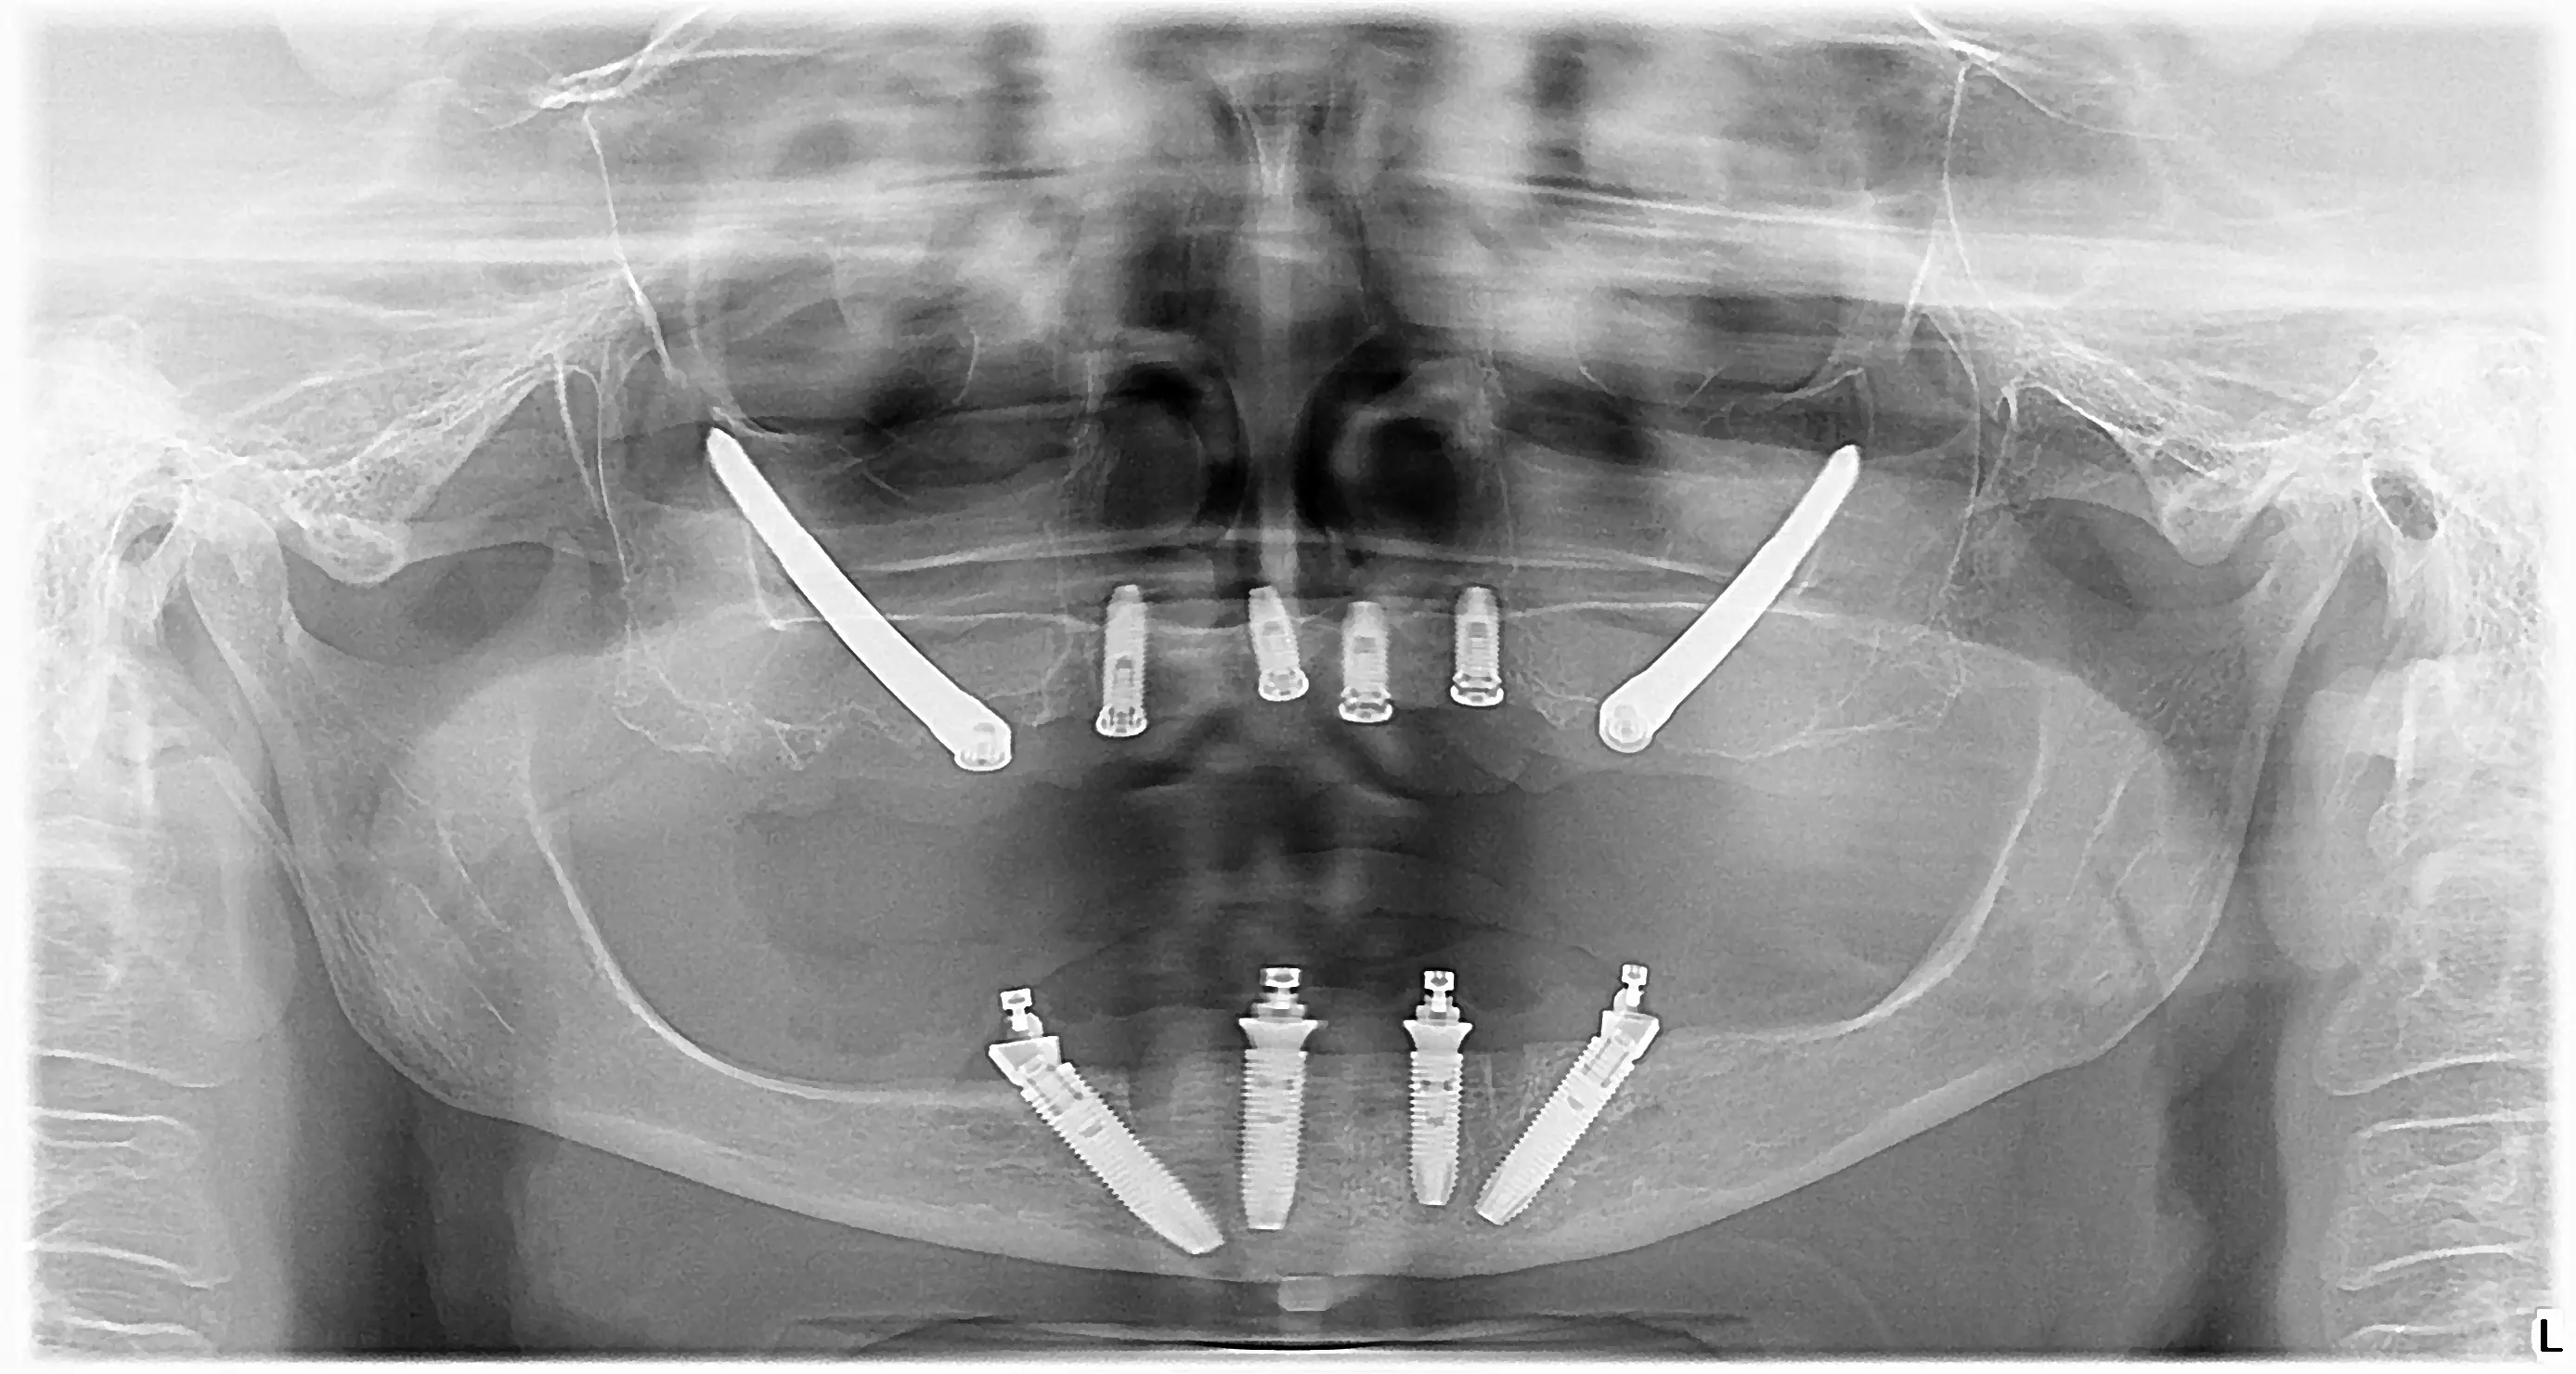

2 zygomatic and 4 Nobel biocare implants in the upper jaw

4 Nobel biocare implants in the lower jaw

We placed two zygomatic implants and 4 Nobel biocare implants in Milanka's upper jaw, thus using the all on 6 method. We placed 4 Nobel biocare implants in the lower jaw using the all on 4 method. We made a hybrid acrylic bridge in both jaws.